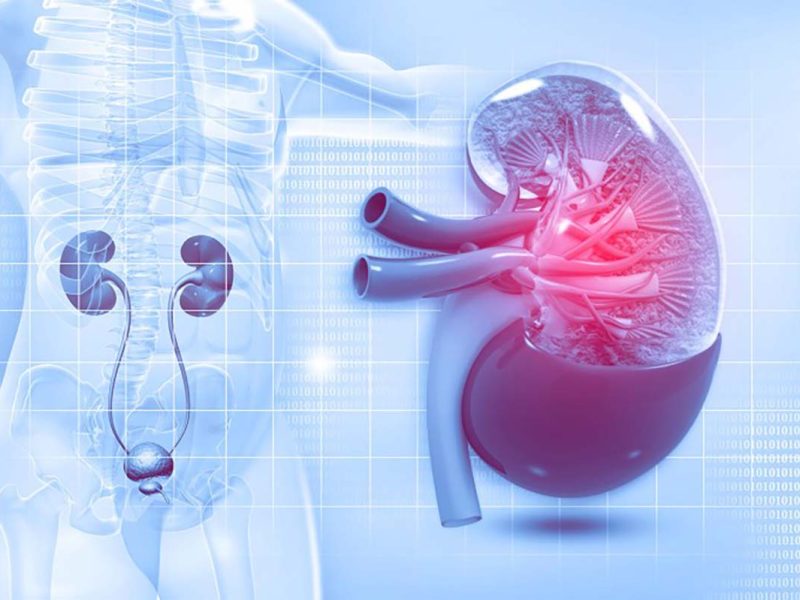

Nephrology & Urology

Our Nephrology and Urology services focus on the diagnosis and treatment of kidney and urinary tract disorders, with integrated support from critical care and dialysis services.